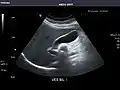

Kidneys: Right and left kidneys measure 11.5 cm and 12 cm in length respectively. No hydronephrosis. Small left lower pole kidney cyst.

Left kidney -